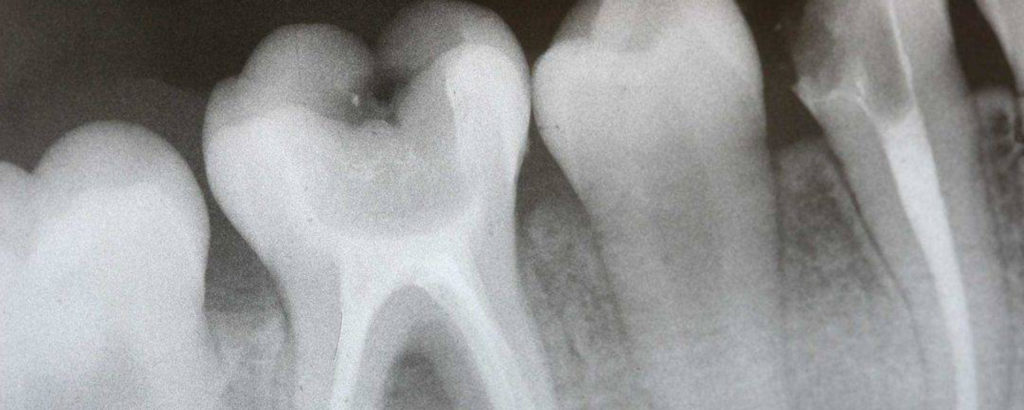

Рентген зуба

Зубные боли, разрушение зубов, появление кариеса – это самые распространённые проблемы, с которыми сталкивается молодая мама из-за нехватки кальция. Далеко не все препараты и витамины, содержащие кальция, разрешены кормящим мамам. А кальций из разрешённых препаратов в основном достаётся малышу. В таких случаях нужно незамедлительно посетить стоматолога, чтобы не размножались болезнетворные микроорганизмы в ротовой полости. Потому что они также попадут к ребёнку через молоко.

Рентген зуба при грудном вскармливании считается безопасным даже для беременных. В современных клиниках используется специальный прибор – визиограф. Эти приборы обладают рядом преимуществ:

- снимки получаются цифровыми;

- площадь поверхности прибора незначительно превышает площадь исследуемого зуба;

- действие его локально непосредственно в ротовой полости.При непрекращающейся зубной боли, необходимо сделать рентген.

Из-за совокупности этих факторов делать рентген в период грудного вскармливания можно. Для защиты от излучения визиографа пациенткам выдают свинцовый фартук, которым необходимо прикрыть грудь и живот.

Поход к стоматологу

Рентген зуба при грудном вскармливании довольно частое явление, так как малютка с первых месяцев своей жизни до полугода получат много питательных веществ из молока матери. Если в организме женщины есть недостаток тех или иных веществ, то это скажется напрямую на её здоровье. Нередко жалобами молодых мам находящихся на гв становится разрушение зубов. Посещение зубного врача подразумевает проведение обследования. Современная медицина не считает опасным исследованием рентген зуба, когда это необходимо кормящей маме. Кроме того, на состав и качество молока и на прохождение лактационного периода данная процедура не влияет. Делать рентген зуба запрещено во время беременности. Так как даже после такого незначительного рентгена возможны нарушения в развитии плода.

Рентгенограмма зуба при лактации

Так как ребёнок кормится за счёт резервов матери, лактирующие женщины часто страдают недостатком кальция. Это проявляется в виде повышенной хрупкости костных структур и зубов.

Стоматологические манипуляции часто предполагают проведение рентгенологического исследования. Это требуется для определения тактики терапии, объёма лечебных манипуляций.

В таком случае можно совмещать рентген зуба и грудное вскармливание. Во-первых, при исследовании область груди защищают специальным свинцовым фартуком, защищающим от проникновения радиоактивного облучения. Во-вторых, площадь облучения слишком мала и доза радиации низкая. При стоматологических манипуляциях необязательно отлучать ребёнка от грудного молока.

Стоматологическое исследование при кормлении грудью

Чаще всего рентген зубов при грудном вскармливании назначают для:

- выявления источника боли или причины искривления,

- просмотра местонахождения пломбы,

- обнаружения очага воспаления или кисты, а также при заболеваниях мягких тканей,

- уточнения возможности сохранения зуба,

- диагностики кариеса.

Стоматологи заверяют, что проведение процедуры при кормлении малыша грудью безопасно и никак не влияет на грудное молоко. Но если есть возможность провести исследование в хорошей клинике с современным оборудованием и минимальной дозой облучения, лучше ее воспользоваться и не подвергать риску себя и грудничка.